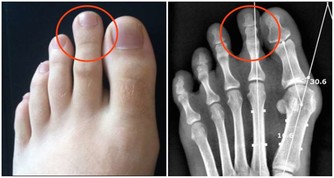

*****1“痛”>腰背痛*****

有些腰背痛,可能是腎結石的信號。

小結石,表現為絞痛,常常突然發生,感覺像刀子在割肉一般,痛感強烈;

較大的結石,常表現為腰部酸脹不適,或在運動時感到隱痛或鈍痛,痛感並不十分強烈。

有的人誤將這種痛當作腰肌勞損,導致病情惡化。提醒大家,身體出現持續的異常,一定要及時上醫院檢查,弄清原因。